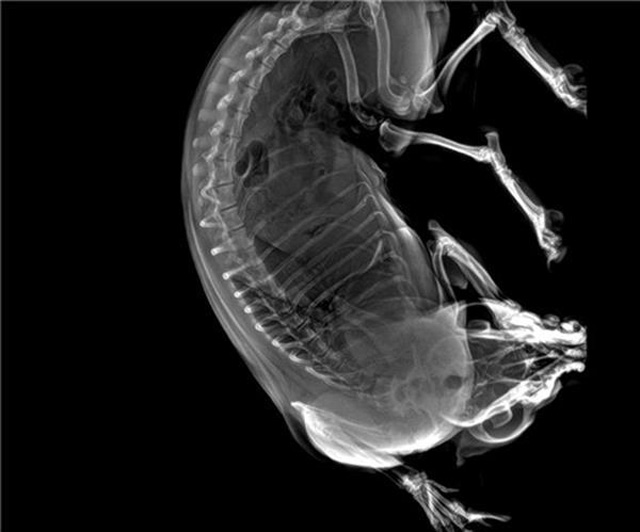

寵物DR的工作原理是X光線穿透動(dòng)物體后在屏幕或者膠片上面顯示體內(nèi)影像。輔助寵物醫(yī)生讀片跟準(zhǔn)確的治療,寵物DR顯示是寵物醫(yī)院診所的配置,提高了診斷的效率。DR的檢測(cè)效率比X線高44%,成像快采集時(shí)間10MS以下。3秒左右就可以看到檢查圖像。常規(guī)的胸部DR還要幾分鐘。所以寵物DR的出片速度是非??斓?。很高的空間分辨率低噪音??梢垣@得高清圖像,提高檢測(cè)正確率避免誤診等等問題。數(shù)字化圖像的優(yōu)勢(shì)是可以保留原始數(shù)據(jù),圖片識(shí)別,二三維的重建,醫(yī)學(xué)影像學(xué)實(shí)現(xiàn)全數(shù)字化和無膠片化鋪平了道路。提供照片打印服務(wù),防止照片丟失而重復(fù)照片。有針對(duì)性的對(duì)圖像進(jìn)行處理,以提高診斷率。寵物DR的輻射量很低的,對(duì)人體的輻射風(fēng)險(xiǎn)不大。